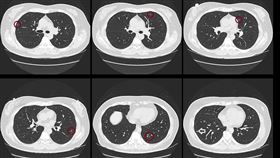

6旬婦滿天星肺結節!「2清潔習慣」出問題

生活習慣錯誤,恐怕會危害到健康!醫師蘇一峰今(17)...

認真消毒惹禍!婦肺部變「毛玻璃狀」

武漢肺炎(COVID-19、新冠肺炎)疫情持續肆虐全...